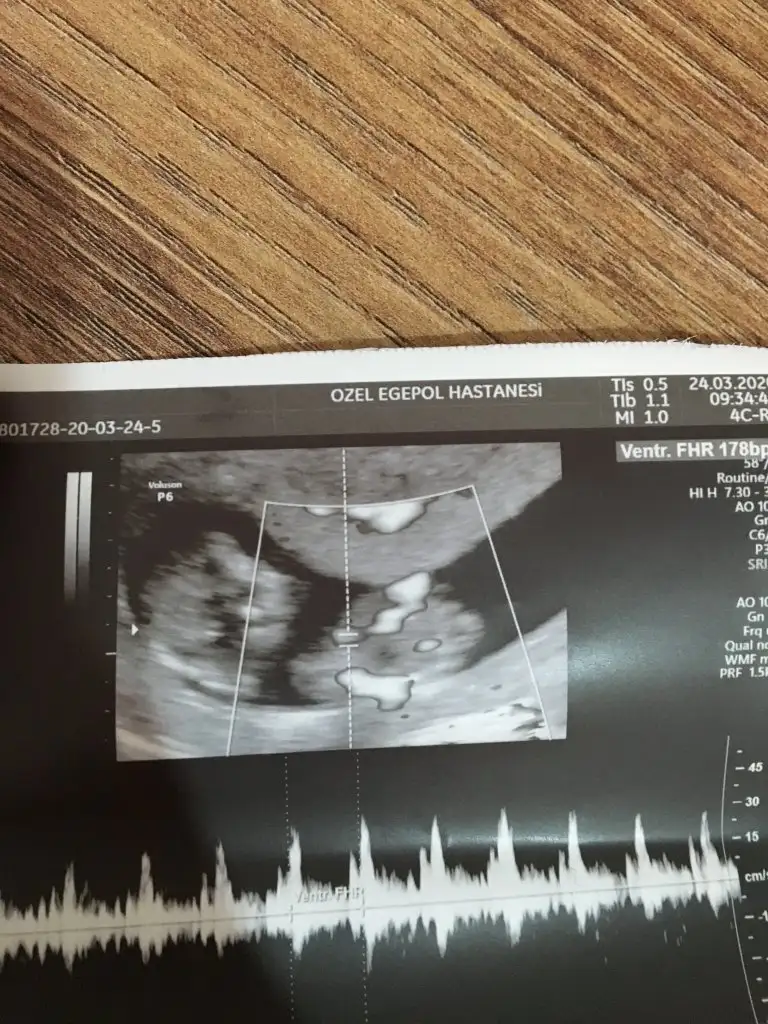

Slm arkadaslar benim bebegimede tahminde bulumabilirmisiniz yurtdisindayim ve burda 5 aydan once soylemiyolar☹️ Merak ediyorum

Usg kaç haftalık erkek gibi net degil usg varsa başka paylaşın

13 haftalik kontrolde verildi resim baska yok neyazikki tek resim bidahaki daha net olur sanirim bende erkek gibi hissesiyorum cin takvimi yumurtlama gunu olmasi bakalim hayirli saglikli dogsunda bir kizim var birde oglum olsun isterim😊sizin tahminler genellikle tutuyor.